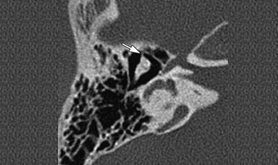

The temporal bone is a pair of bones on the sides of the human skull which houses the middle and inner ear. High Resolution Computed Tomography (HRCT) is highly effective in demonstrating the anatomy and pathology of the temporal bone. In order to obtain the proper diagnosis in infants and children, both the axial and coronal planes is taken utilizing HRCT.

The following are the indications for which CT HRCT is used

- Temporal bone fractures

- Acute temporal bone trauma

- Congenital anomalies

- Inflammatory processes

- Traumatic lesions

- Tumors